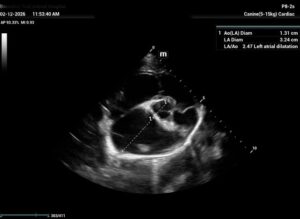

Chronic stage C MVD.TID Pimo and Lasix(high dose), ACEi and Spirono. Doing well. Recheck: Idexx GHP= CBC-NSF ,SDMA 15,BUN 14.1mmol/L, Creat 79umol/L. US: Cornell Indx LVd=1.46(prev2.1), LV septal flattening with diastolic dip,LAAO=2.47,Evel1.45m/s, TVregPG-68mmHg,HV distension-mod ascites.LV and LA underloading via diuretics and PHT (mild PHT past).PHT more pre vs post cap based on small LVsize? Consider Sildenafil/L Arg.Concerned about developing L CHF.Is CHF less likely adding PDE5i with MVD/PHT in underloaded LV than same scenario with vol overloaded LV at similar staging. MVPG=120.3mmHg

Dan, considering the LAE in addition to LV underloading – does this dog have mitral stenosis?? As you suggested, with this degree of LAE I would expect LVE as well….

Thanks. Not sure if any sig. MV stenosis?? My experience limited.3 PWD from diff times. Ls7 vid. is from 2024,initially thinking reverse remodelling where the lasix lowering preload and Pimo is decreasing LV size via decreased resist/increase cxn while LA no change because it’s a chronic filled remodeled saggy bag receiving Regurge volume??